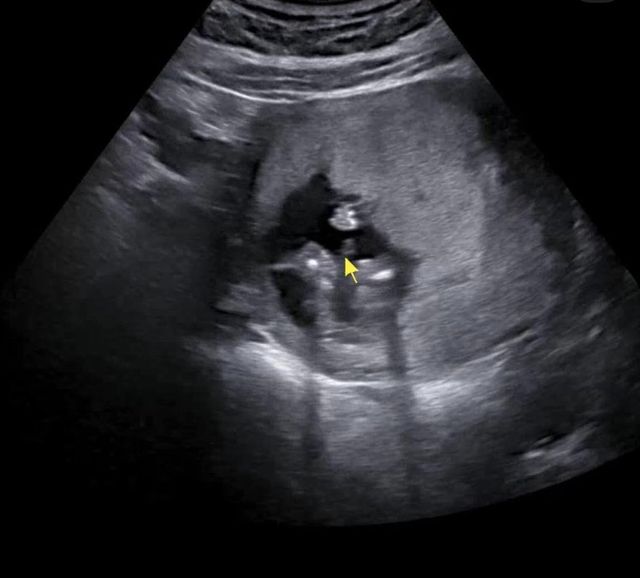

지난주 주말에 가서 확인했는데, 와이프랑 저랑 확인하기전부터 계속 딸이였음 싶다가 아들인거 확인하구, 아들이면 어떻구 딸이면 어때! 하면서 그저 무사히 건강하게만 나와줫음 싶은 마음으로 주말 보냈습니다!

와이프 임산부복 사러 간김에 겸사겸사 애기 첫 옷도 사왔어요! 2차 기형아검사 이번주에 나오는데 부디 별 탈 없기를 바래봅니다! 다들 이번 한 주도 힘내새요!